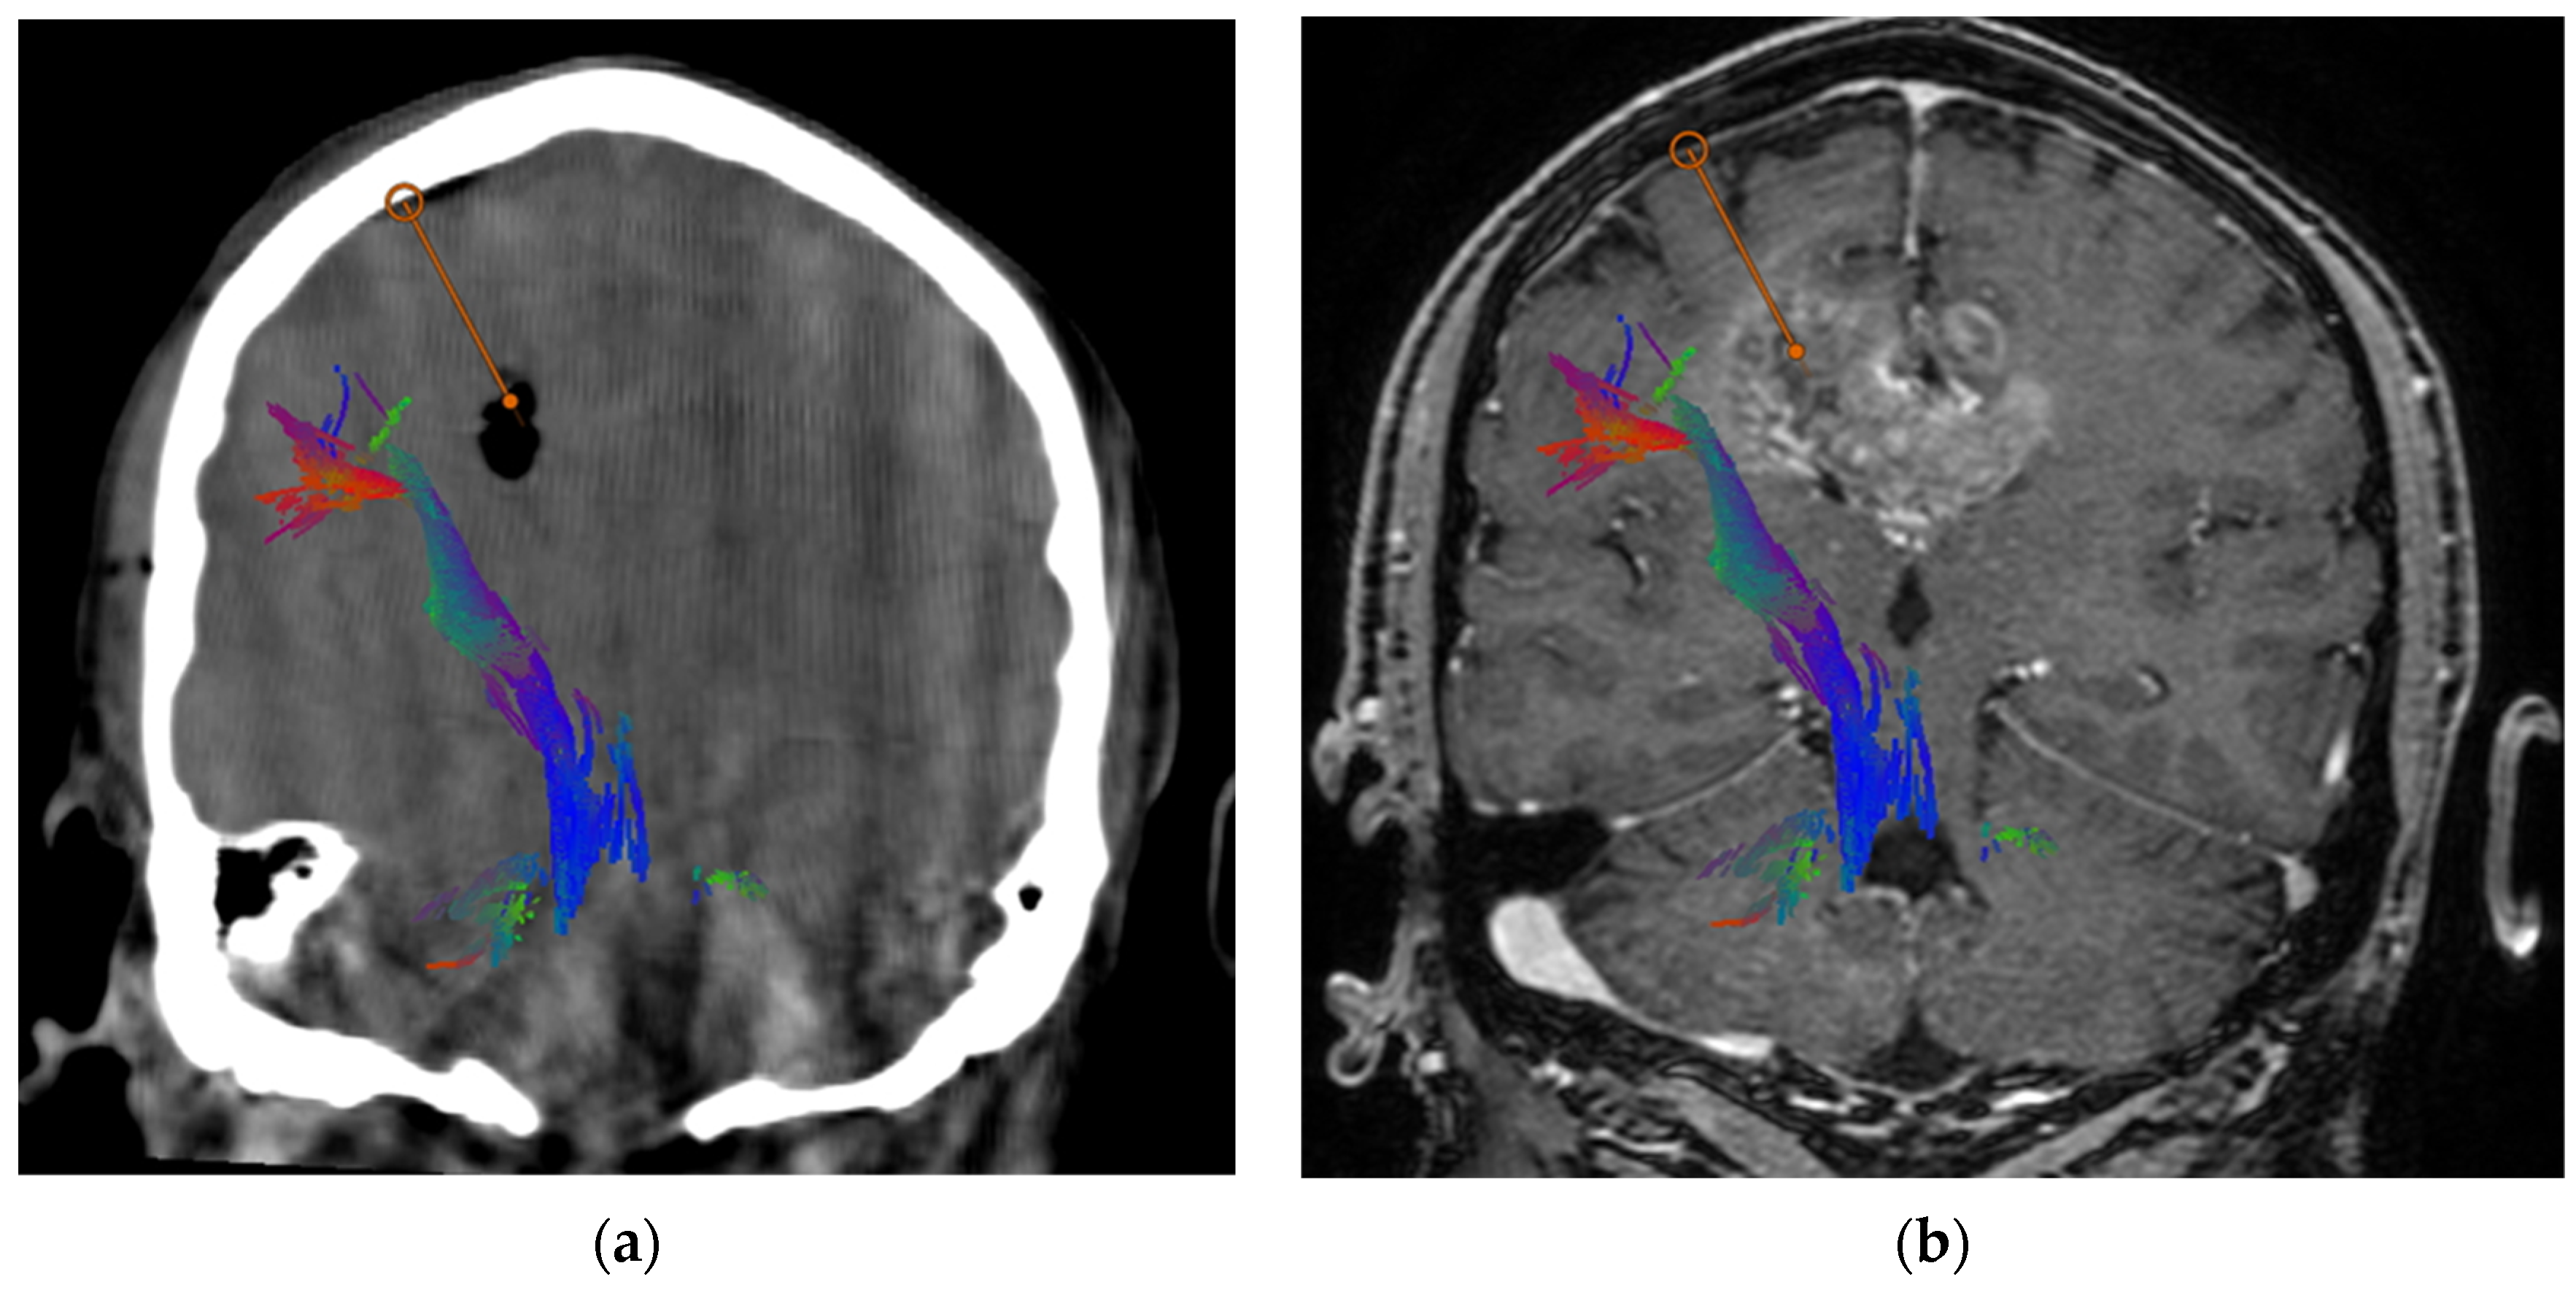

- Mazzucchi, E.; La Rocca, G.; Hiepe, P.; Pignotti, F.; Galieri, G.; Policicchio, D.; Boccaletti, R.; Rinaldi, P.; Gaudino, S.; Ius, T.; et al. Intraoperative Integration of Multimodal Imaging to Improve Neuronavigation: A Technical Note. World Neurosurg. 2022, 164, 330–340. [Google Scholar] [CrossRef]

- Della Pepa, G.M.; Ius, T.; La Rocca, G.; Gaudino, S.; Isola, M.; Pignotti, F.; Rapisarda, A.; Mazzucchi, E.; Giordano, C.; Dragonetti, V.; et al. 5-Aminolevulinic Acid and Contrast-Enhanced Ultrasound: The Combination of the Two Techniques to Optimize the Extent of Resection in Glioblastoma Surgery. Neurosurgery 2020, 86, E529–E540. [Google Scholar] [CrossRef] [PubMed]